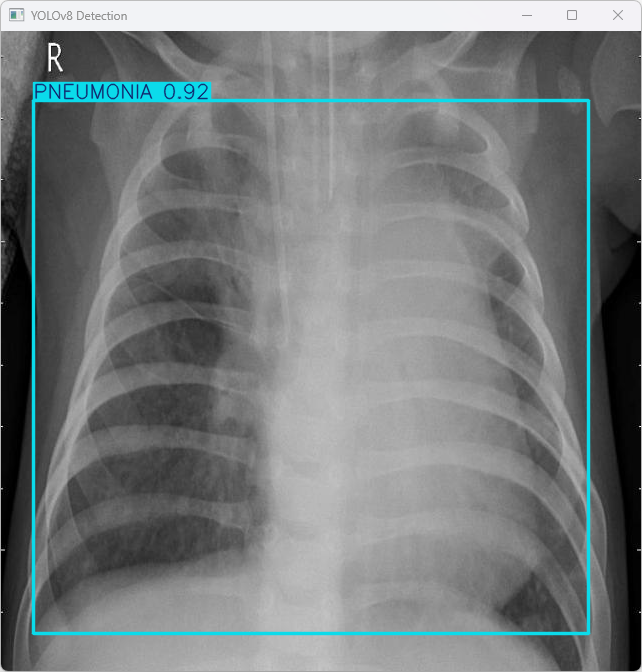

执行imgTest.py代码后,会将执行的结果直接标注在图片上,结果如下:

该系统利用YOLOv8模型对图像文件imagetest.jpg进行识别,并具体信息如下:

图像信息:

(1)处理的图像路径为:TestFiles/imagetest.jpg。

(2)图像尺寸为640×640像素。

检测结果:

(1)检测到 1 个 PNEUMONIA(检测出图像中含有肺炎特征)。

处理速度:

(1)预处理时间: 7.0 毫秒

(2)推理时间: 5.0 毫秒

(3)后处理时间: 86.0 毫秒

总结:

模型识别出肺炎特征,并在完成预处理、推理和后处理的过程中实现了高效的速度。该系统展示了快速响应能力,在实际应用场景中具有良好的适用性。